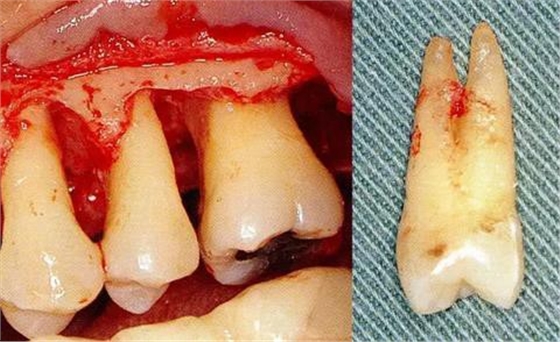

▼圖6-1下頜第一后磨牙的頰舌間存在III度的根分叉病變,預(yù)在進(jìn)行牙根分割后保留遠(yuǎn)中根。

▼圖6-2中下頜第一后磨牙雖然切除了一半,但是遠(yuǎn)中根也有2根分根,所以不得已拔除(被拔除遠(yuǎn)中根的近中面觀察)。